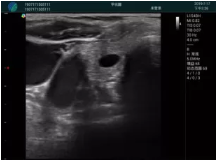

清晰顯示腺體內(nèi)低回聲快影,邊界清晰,包膜較光滑

確定進(jìn)針路徑并實(shí)時監(jiān)測抽吸針與腫塊位置關(guān)系

抽吸針進(jìn)入腫塊內(nèi)部進(jìn)行旋切

抽吸過程中可見腫塊明顯縮小,并根據(jù)腫塊位置改變針道位置

抽吸旋切后再進(jìn)行超聲復(fù)查,原腫塊區(qū)域未見殘留組織及出血